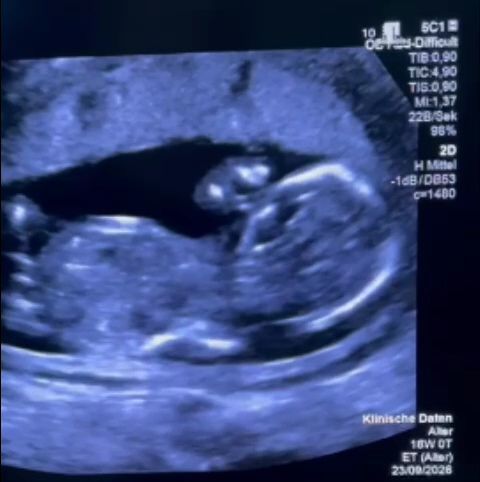

Fostul secretar de stat în Ministerul Sănătăţii Monica Althamer, director de program în cadrul Fundaţiei Metropolis, relatează cazul unei femei însărcinate care a aflat, în săptămâna a 12-a, despre o malformaţie minoră, pentru care există tratament. Părinţii au cerut informaţii şi au ales să facă tratamentul necesar la Spitalul Filantropia din Bucureşti. Ajunşi la unitatea medicală, însă, au avut parte de tratament degradant, nu li s-au oferit informaţii şi, în plus, li s-a recomandat să aştepte, deşi un medic german a transmis că procedura este de făcut urgent. Când au cerut eliberarea de documente care să le permită să facă tratamentul gratuit în străinătate au fost, de asemenea, refuzaţi. De Paştele catolic, oamenii au ajuns în Germania, iar procedura a fost făcută a doua zi de către un specialist german, care vorbeşte despre ”o consiliere extrem de slabă” făcută în România.